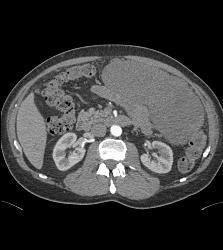

GIST Tumor